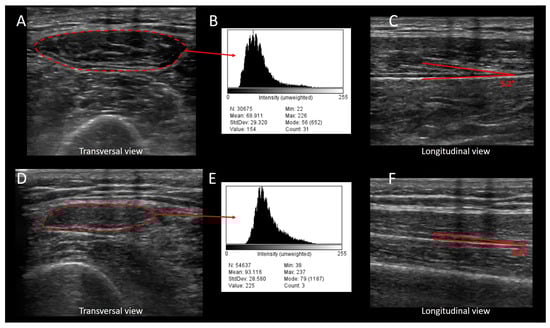

- Albayda, J.; van Alfen, N. Diagnostic Value of Muscle Ultrasound for Myopathies and Myositis. Curr. Rheumatol. Rep. 2020, 22, 82. [Google Scholar] [CrossRef]

- Pillen, S.; van Keimpema, M.; Nievelstein, R.A.; Verrips, A.; van Kruijsbergen-Raijmann, W.; Zwarts, M.J. Skeletal muscle ultrasonography: Visual versus quantitative evaluation. Ultrasound Med. Biol. 2006, 32, 1315–1321. [Google Scholar] [CrossRef]

- Schneider, C.A.; Rasband, W.S.; Eliceiri, K.W. NIH Image to ImageJ: 25 years of image analysis. Nat. Methods 2012, 9, 671–675. [Google Scholar] [CrossRef] [PubMed]

- Harris-Love, M.O.; Seamon, B.A.; Teixeira, C.; Ismail, C. Ultrasound estimates of muscle quality in older adults: Reliability and comparison of Photoshop and ImageJ for the grayscale analysis of muscle echogenicity. PeerJ 2016, 4, e1721. [Google Scholar] [CrossRef] [PubMed]

- Puthucheary, Z.A.; Phadke, R.; Rawal, J.; McPhail, M.J.W.; Sidhu, P.S.; Rowlerson, A.; Moxham, J.; Harridge, S.; Hart, N.; Montgomery, H.E. Qualitative Ultrasound in Acute Critical Illness Muscle Wasting. Crit. Care Med. 2015, 43, 1603–1611. [Google Scholar] [CrossRef]